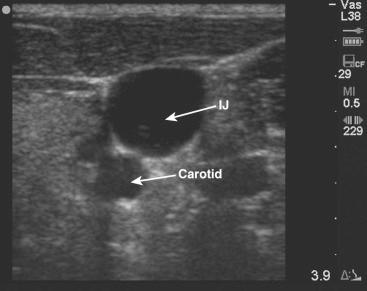

The indirect method employs the least amount of actual guidance. With this approach, US is used only to identify the vessel and then center it on the US screen ( Figure 69-2-1 ). Next, a temporary mark is placed on the skin that corresponds to the vessel's subcutaneous position. This mark is used for the puncture site after US identifies the target vessel's location, dimensions, and depth below the skin. The easiest way to accurately make this mark is to identify the point where the center of the transducer overlies the skin surface just above the center of the vessel ( Figures 69-2-2 and 69-2-3 ).

F igure 69-2-1, IJV and carotid artery viewed in their short axes.